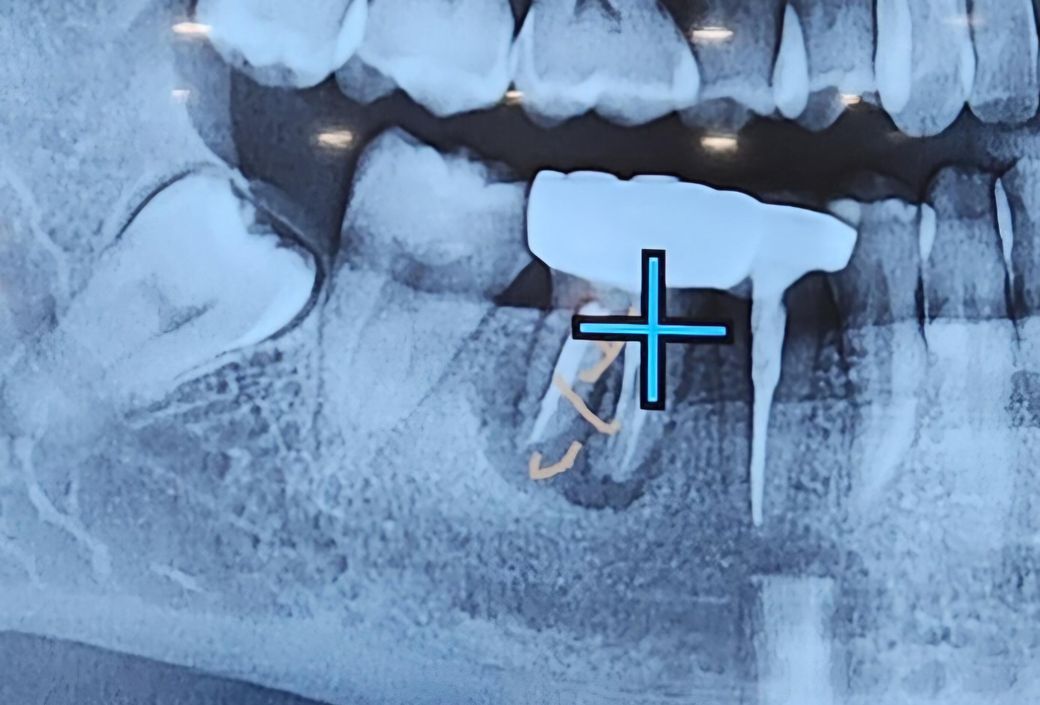

치과에서 첨부 사진의 십자가 커서가 위치한 곳의 크라운 치아의 상태가 매우 좋지 않다고 뼈이식 및 임플란트 식립을 추천하시던데요. 현재 해당 치아가 아프거나 불편하지는 않은 상태인데 임플란트를 당장 하는 것이 좋은 걸까요?

만성염증 그리고 신경치료가 된 치아이므로 통증이 없을 수도 있으나 엑스레이상으론 잇몸뼈가 녹기 시작했을 정도로 치아 뿌리 주면 염증이 있습니다.

크라운 씌운쪽 치아 안쪽도 삭아있습니다. 크라운을 씌운 치아의 옆쪽(mesial) 치아면이 뚜렷하지 않은 것을 보실 수 있는게 그게 충치로 치아가 삭은 것입니다.

그로 미루어보아 신경치료하고 크라운씌운지도 꽤 된 듯 한데 아직 염증이 저런 상태라면 앞으로도 나빠질 확률이 높습니다. 잇몸뼈가 너무 많이 녹으면 추후 임플란트 심는 난이도가 올라갑니다.

사진으로 봤을 경우에는 치아뿌리에 치조골이 많이 손상된 것으로 보입니다. 치주 질환이나 치아 파절로 인해서 손상되었을 가능성을 높으며 치아를 유지하고 있는 치조골이 없다면 치아는 발치를 할 수밖에 없습니다

잇몸뼈가 너무 많이 녹고 뿌리까지 녹아서 발치후에 염증제거하고 골이식 및 임플란트를 하셔야 합니다. 증상이 없는경우도 종종 있지만 그대로 두시면 염증이 번져서 어느날 갑자기 볼이 퉁퉁 부을 수도 있고 봉와직염이, 나아가 근막간극농양으로 번지는 경우도 있습니다. 빠르게 치료받으시는 것이 좋겠습니다.